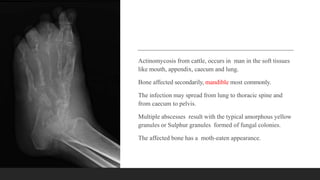

Actinomycosis from cattle, occurs in man in the soft tissues

like mouth, appendix, caecum and lung.

Bone affected secondarily, mandible most commonly.

The infection may spread from lung to thoracic spine and

from caecum to pelvis.

Multiple abscesses result with the typical amorphous yellow

granules or Sulphur granules formed of fungal colonies.

The affected bone has a moth-eaten appearance.